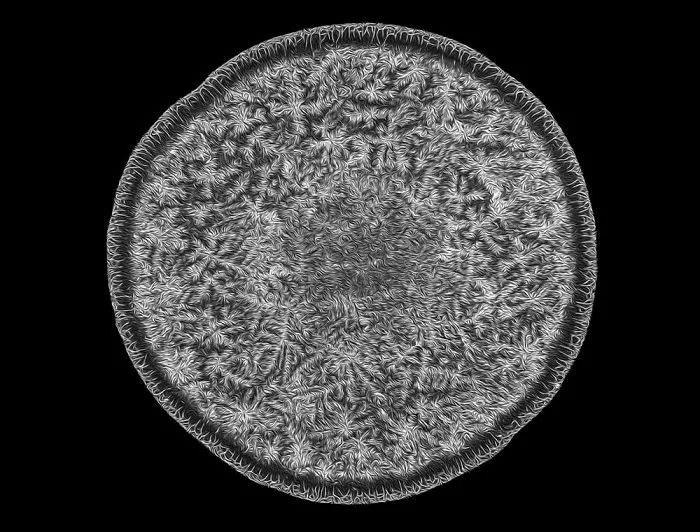

人类视网膜

第20名:人类视网膜(Nicolás Cuenca 和 Isabel Ortuño-Lizarán/ 摄)Nicolás Cuenca 和 Isabel Ortuño-Lizarán来自西班牙阿利坎特大学